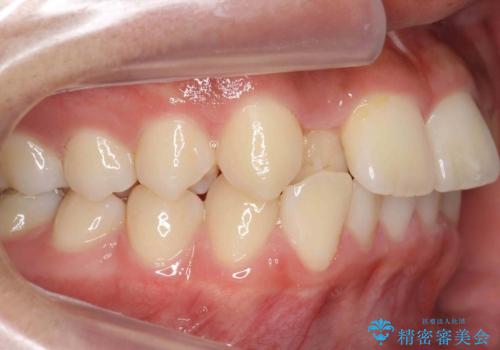

- ワイヤー矯正による治療後7年以上経過した患者様です。当時上の小臼歯を2本抜歯しています。

矯正後8年目になりますが、並びも綺麗に保持でき、また上下の歯がさらにしっかり咬んできているのがわかります。

定期的にメンテナンスにきていただき、特に歯の健康状態にも問題がありません。